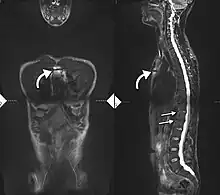

Imaging

X-rays

The earliest changes demonstrable by plain X-ray shows erosions and sclerosis in sacroiliac joints. Progression of the erosions leads to widening of the joint space and bony sclerosis. X-ray spine can reveal squaring of vertebrae with bony spur formation called syndesmophyte. This causes the bamboo spine appearance. A drawback of X-ray diagnosis is the signs and symptoms of AS have usually been established as long as 7–10 years prior to X-ray-evident changes occurring on a plain film X-ray, which means a delay of as long as 10 years before adequate therapies can be introduced.[26]

Options for earlier diagnosis are tomography and MRI of the sacroiliac joints, but the reliability of these tests is still unclear.

Lateral X-ray of the mid back in ankylosing spondylitis

Lateral X-ray of the neck in ankylosing spondylitis

X-ray showing bamboo spine in a person with ankylosing spondylitis

CT scan showing bamboo spine in ankylosing spondylitis

T1-weighted MRI with fat suppression after administration of gadolinium contrast showing sacroiliitis in a person with ankylosing spondylitis